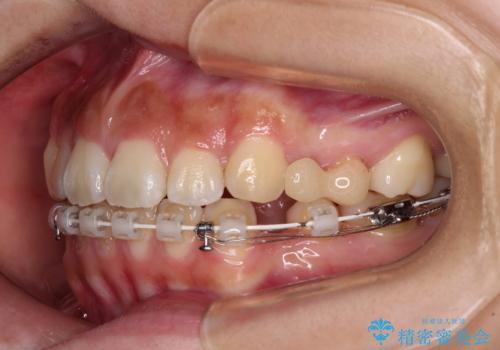

- ハーフリンガル

- 3年2ヶ月

- 30回以上

上下前歯が嘴のように前方に突出しており、唇が閉じにくい状態であったため、上下左右の第一小臼歯4本を抜歯して、口元の突出感を改善することとしました。

目立たない装置を希望とのことで、上顎が裏側、下顎が表側のハーフリンガル装置を用いることとしました。